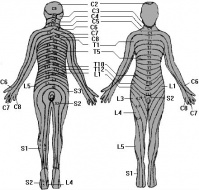

S24.2 Травма на нервните коренчета на гръдната част на гръбначния стълб

Увреждане на коренчетата на нервите от травма в областта на гръдния кош е травма на нервните коренче...

S24.3 Травма на периферните нерви на гръдния кош

Периферните нерви на гръдния кош са гръбначни нерви излизащи през отвори на гръдните прешлени на гръ...

S24.5 Травма на други нерви на гръдния кош

Други нерви на гръдния кош могат да бъдат повредени при различни травматични обстоятелства както са ...

S24.6 Травма на неуточнени нерви от гръдния кош

Нервите на гръдния кош могат да се засегнат при всяка тъпа или открита травма на гръдния кош. Травма...